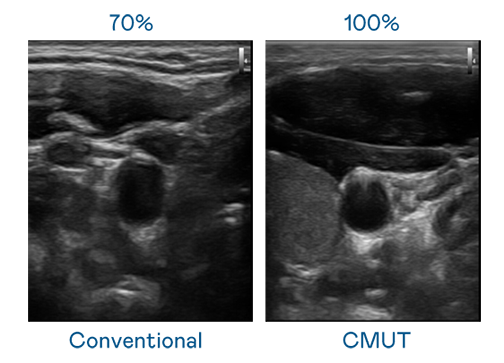

CMUT 技术是一种用电容式微机电元件来产生超音波讯号的技术。与传统 PZT 压电式技术相比,CMUT 频宽增加 30%,更宽频的超音波讯号让影像解析度大幅提升,是实现高影像品质医疗超音波扫描、促进精准医疗发展的关键技术。

大频宽带来超清晰影像

超音波影像的解析度高低,首先取决于探头能发出的讯号频宽。四级杀人狂完整版电影在线播放 CMUT 可提供高清晰的超音波讯号,提供高频宽、高灵敏度、影像纹理细节更高的超音波影像,协助医护人员缩短影像判读时间及利用精准的医疗影像进行诊断。